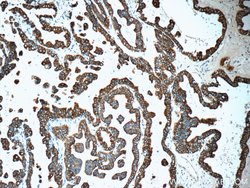

This antibody is specifically against KRT7.

| Immunocytochemistry, Immunofluorescence, Immunohistochemistry (Paraffin), Immunoprecipitation, Western Blot | |